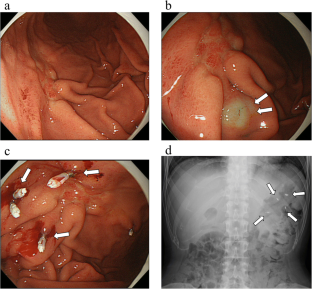

Fig. 1

Fig. 2

Fig. 3